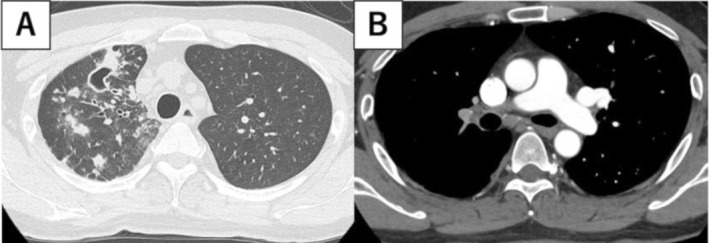

39岁男性,发热、呼吸困难1周。影像学提示右肺浸润性细菌性肺炎。然而,尽管使用抗生素,症状仍然存在。支气管镜检查显示凝固性坏死,增强计算机断层扫描发现右肺动脉有大血栓,诊断为肺梗死。患者直接口服抗凝剂治疗。两年后,在右肺上叶观察到新的结节性病变伴空洞。支气管镜检查显示鸟分枝杆菌感染。我们假设非结核性分枝杆菌(NTM)肺病可能并发慢性肺栓塞。

A 39-year-old man presented with fever and dyspnoea for 1 week. Imaging suggested bacterial pneumonia with infiltrates in the right lung. However, the symptoms persisted despite antibiotics. Bronchoscopy revealed coagulation necrosis, and enhanced computed tomography identified a large thrombus in the right pulmonary artery, leading to a diagnosis of pulmonary infarction. The patient was treated with direct oral anticoagulants. Two years later, new nodular lesions with cavities were observed in the upper lobe of the right lung. Bronchoscopy revealed a Mycobacterium avium infection. We hypothesise that nontuberculous mycobacterial (NTM) pulmonary disease may complicate chronic pulmonary embolism.